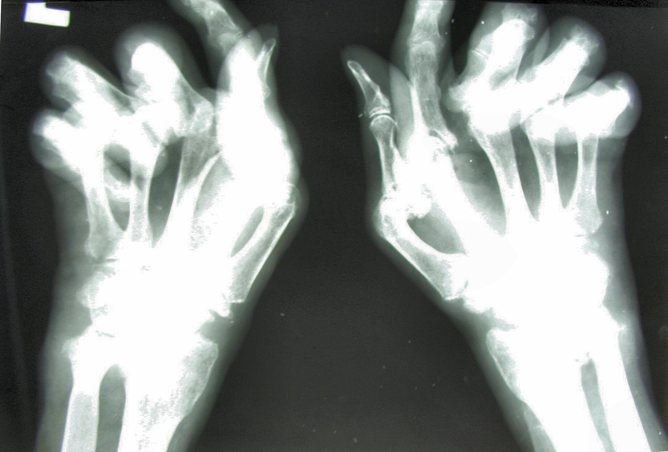

So what is rheumatoid arthritis? Those afflicted suffer pain, swelling and progressive deformity of joints if untreated.

The core problem seems to be uncontrolled inflammation – the immune system that normally faithfully defends us against infection turns its offensive molecular and cellular power upon the joints, which leads to substantial damage.

There is no cure. Rheumatoid arthritis progresses inexorably over time, causing sufferers to lose function, independence and ultimately years of life expectancy. The disease is associated with loss of work productivity, employability and increased health care costs, so there is also an increased financial burden on family and community.